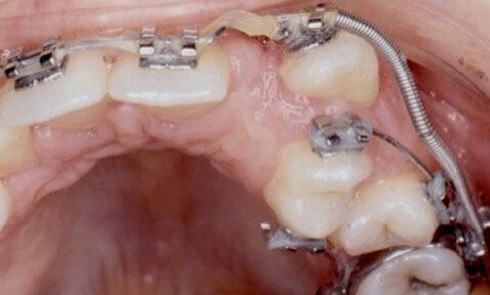

Article réservé à nos abonnés Désinclusion d’une deuxième molaire mandibulaire à l’aide d’un Abalakov

3e lauréat du Grand Prix de l’Orthodontiste – Orthoplus Diagnostic Julien nous consulte à l’âge de 11 ans et 4...